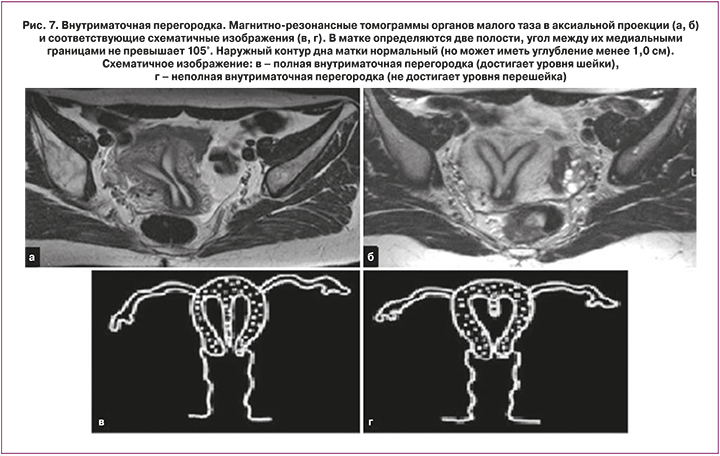

V класс. Внутриматочная перегородка

Среди мальформаций женских половых путей внутриматочная перегородка встречается наиболее часто и является наиболее частой причиной акушерских осложнений [5, 11, 13, 18]. Эта аномалия является результатом отсутствия резорбции (полного или частичного) срединной сагиттальной перегородки. Перегородка берет свое начало на уровне центральных отделов дна матки широким или узким основанием и состоит преимущественно из мышечной и фиброзной тканей. При полной форме внутриматочная перегородка распространяется до внутреннего зева или даже на влагалище [7]. Наружный контур дна матки может быть обычным, плоским или незначительно вогнутым, без выраженного углубления и существенного расхождения рогов матки. МРТ позволяет четко визуализировать внутриматочную перегородку, обеспечивает точную информацию о степени мальформации, толщине перегородки, соотношении мышечной и фиброзной тканей, что очень важно при планировании хирургического вмешательства [12, 13]. Кроме того, МРТ позволяет четко дифференцировать данную аномалию от двурогой матки (рис. 7).

Ключевые признаки: при наличии внутриматочной перегородки матка имеет обычные размеры. Наружный контур дна матки, в отличие от аномалий слияния мюллеровых протоков, имеет, как правило, нормальный слегка выпуклый контур. Оценка наружного контура дна матки является ключевым моментом в дифференциальной диагностике аномалий слияния парамезонефральных протоков от аномалий резорбции срединной сагиттальной перегородки. Дифференциальная диагностика внутриматочной перегородки от двурогой матки крайне важна во избежание излишних хирургических вмешательств, например, гистероскопической септопластики у женщин с двурогой маткой.

Интенсивность МР-сигнала от внутриматочной перегородки на Т2 ВИ зависит от соотношения в ней фиброзной и мышечной ткани. При преобладании фиброзной ткани, перегородка выглядит более гипоинтенсивной к миометрию, при преобладании мышечной ткани – изоинтенсивной. Преобладание мышечной или фиброзной ткани имеет очень большое значение в планировании хирургического вмешательства. При внутриматочной перегородке с преобладанием фиброзной ткани проводится гистероскопическая септопластика, в то время как внутриматочная перегородка с преобладанием мышечной ткани при отсутствии репродуктивных потерь зачастую не требует хирургической коррекции [19].